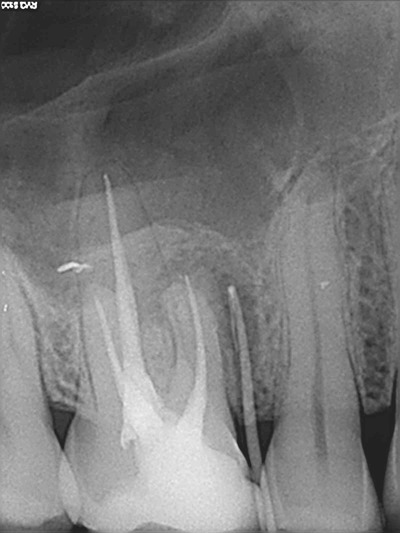

Потом я нашла врача для распломбировки каналов и 26 августа мне распломбировали каналы и положили в каналы кальцийсодержащую пасту на турундах. Рентген после распломбировки каналов.